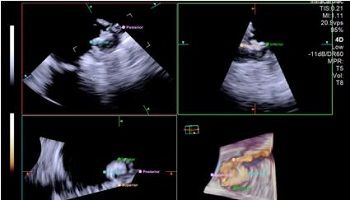

(사진 : 4D 심장내초음파를 활용한 좌심방이폐색술 시술 영상 예시)

4D 심장내초음파는 심장 내부의 구조를 실시간으로 정밀하게 보여주는 고해상도 영상 기술로, 기존 2D 심장내 초음파에 비해 다양한 각도에서 더 정밀한 해부학적 정보를 제공한다.

이러한 입체적인 영상 기술을 활용하면 시술자가 심장과 장치의 구조를 더욱 정확하게 파악할 수 있어서 시술의 효율성과 안전성이 개선될 수 있다.